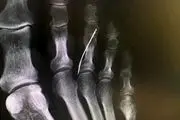

بی خبری از وجود سوزن خیاطی داخل پای این پیرزن! + عکس

پیرزنی به طور بسیار باورنکردنی و عجیب از رفتن سوزن خیاطی به داخل پای خودش اطلاع نداشت.